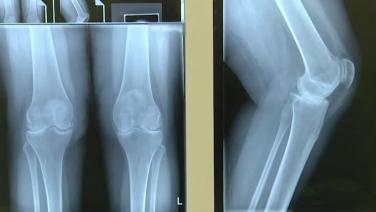

ATTUNE® Rotating Platform: Pre-Operative Evaluation with Peter James, MD

Knee Replacement Anatomical Poster